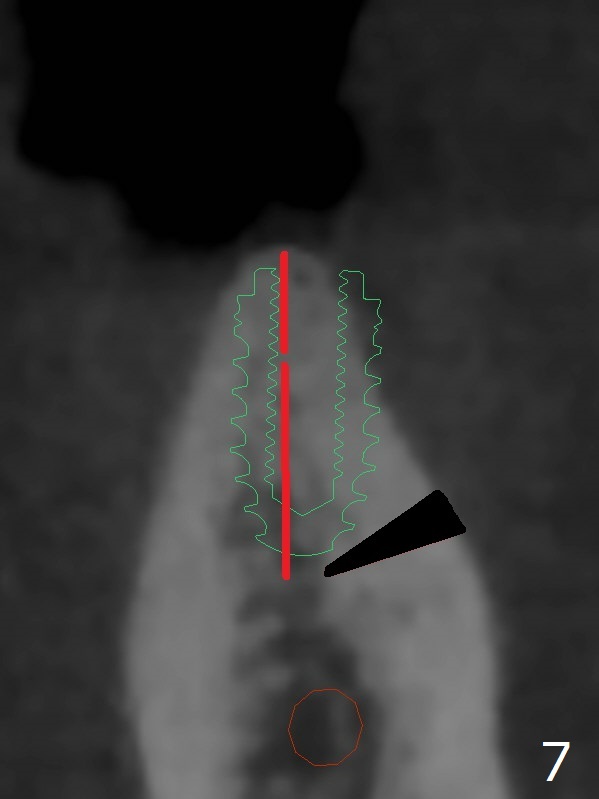

When implants at #4, 13 and 14 are placed, the patient wonders how many more implants are needed. From 0 (considering a lower RPD) to 5 (#3, 19, 20, 25 and 30). The tooth #3 seems to have periodontal-endodontic disease (Fig.1,2). Since the ridge is narrow at #19 and 20 (Fig.3), ridge split at #19 and a 1-piece implant at #20 are planned (Fig.4,5-9). The implant at #19 will be placed in an ideal prosthetic position (Fig.5). The ridge transverse bony cut will be made free hand in the middle (Fig.6,6'), followed by 2 vertical cuts and 1 apical transverse one in the 1st stage of procedure. In order to rotate the buccal block easier (Fig.6 pink curved arrow), the apical transverse cut will be wedge in shape (Fig.6 (red), 6' (double lines), 7 (black)). In the 2nd stage, the ridge top split will be extended by using a chisel (Fig.7 longer red line) and the buccal block will be pushed buccally (Fig.8). A guide will be seated to finish osteotomy (Fig.9 white) and implant placement.